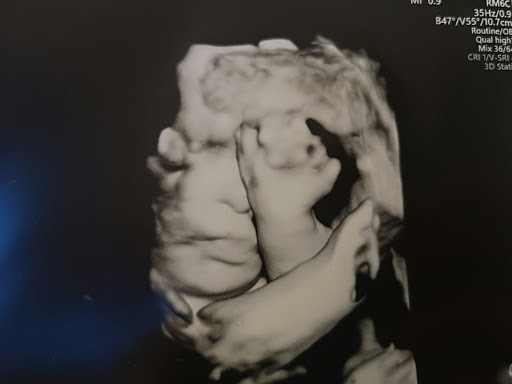

Vaikka tunnenkin jo ennestään yhden down-ihmisen niin minulla oli ja on vieläkin hirveän paljon epätietoa. Todella paljon kysymyksiä joihin kukaan ammattilainen ei minulle osannut vastata. Aina vaan luettiin niitä samoja tilastoja, mutta ei tullut mitään konkreettista tietoa mitä olisin kaivannut. Miten siis vanhemmat, jotka saavat tietää odottavansa down-vauvaa, selviytyvät kun tietoa ei tule juuri mistään? Tai ylipäätään sitä tukea, kunnon tietoa asioista. Sitä olisin kaivannut, toki kyllä halusin tietää liitännäissairauksistakin mutta olisin kaivannut myös jotain muuta. Tietoa vauva-ajasta, elämästä, arjesta ja millaista se elämä, arki oikeasti on sen down-lapsen kanssa.

Nämä ovat siis minun kokemuksiani ja siinä tunnen jääneeni ilman tukea. Se harmittaa minua kauheasti, koska juuri silloin sillä hetkellä olisin kaivannut sitä tukea ja tietoa. Meillä meni muuten kuitenkin hyvin ja olemme sopeutuneet hyvin tähän elämän tilanteeseen. Meillä on todella ihana tytär. ❤️ Vielä ei tiedetä mitä tämä elämä meille tuo ja kuinka paljon tukea Meea oikeastaan tarvitsee tulevaisuudessa, mutta me menemme hetki kerrallaan. Tällä hetkellä meillä on hyvä olla ja nautimme vauva-ajasta tai ainakin yritän olla stressaamatta turhia. Mikä on kyllä vähän vaikeasti tehty, kun olen kova stressaamaan. Jerkku sitä sitten joutuu kuuntelemaan, olen muutenkin aika temperamenttinen. Liekköhän Meea perii sen äidiltään. 😂